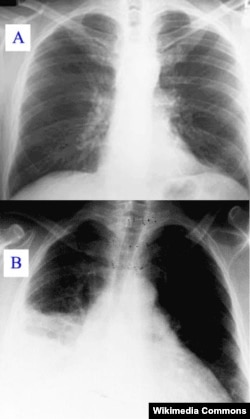

Sinar-X menunjukkan paru-paru yang bersih (A) dan paru-paru yang terinfeksi pneumonia (B)